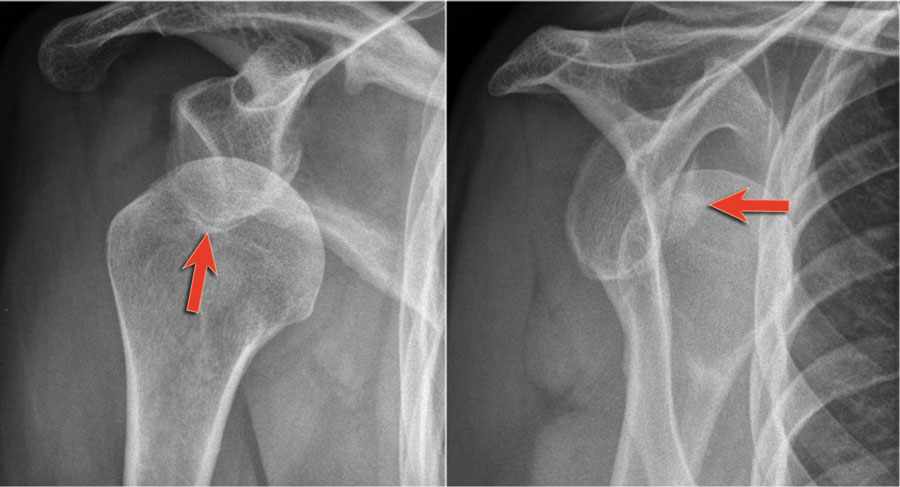

Các hình ảnh cho thấy một gãy xương Bankart kín đáo (mũi tên).

Gãy xương Bankart

Đây là hình ảnh sau nắn chỉnh.

Lưu ý đường gãy rất lớn của bờ ổ chảo kèm di lệch mảnh gãy.

Trên tái tạo mặt phẳng chếch vành tai và mặt phẳng đứng dọc, mảnh gãy di lệch của bờ ổ chảo được thấy ở vị trí 3-6 giờ.

Trên hình ảnh mặt phẳng vành tai, quan sát thấy một khuyết xương Hill-Sachs lớn.

Đây là khuyết xương do hậu quả của sự va đập bờ ổ chảo vào chỏm xương cánh tay.